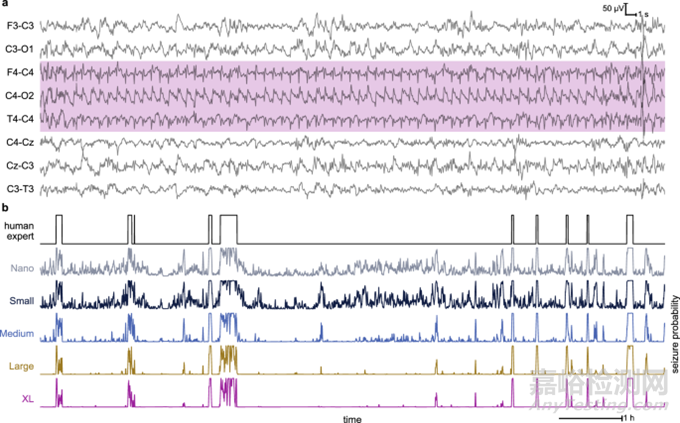

圖片節(jié)選:癲癇發(fā)作時(shí)的腦電圖片段及不同模型輸出的比較[1]

a)來自開發(fā)數(shù)據(jù)集的 60 秒 EEG 樣本,每個(gè)通道的癲癇發(fā)作注釋都以陰影顯示。在此示例中,只有 3/8 個(gè)通道包含癲癇發(fā)作。

b)相同EEG 記錄中 C4-O2 的 10 小時(shí)注釋和模型輸出。

(a)中的 EEG 樣本對(duì)應(yīng)于(b)中第一次癲癇發(fā)作事件的前 60 秒。不同規(guī)模的模型(即微型、小型、中型、大型和超大型 (XL) 模型)變得更加可信,可以抑制非癲癇發(fā)作期的輸出,同時(shí)在癲癇發(fā)作期保持高度一致性。這種易于解釋的特性將有利于使用實(shí)時(shí)模型輸出跟蹤的臨床實(shí)施。